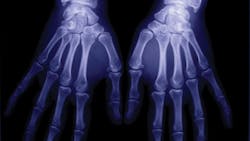

The human hand contains 27 intricate bones, and are the main structures for physically manipulating the environment, used for both gross motor skills (grasping a large ball-peen hammer) and fine motor skills (picking up a loose roofing nail or scalpel). In addition, the fingertips contain some of the densest areas of nerve endings on the body, are the richest source of tactile feedback and have the greatest positioning capability of the body. The sense of touch intimately is associated with the human hand.